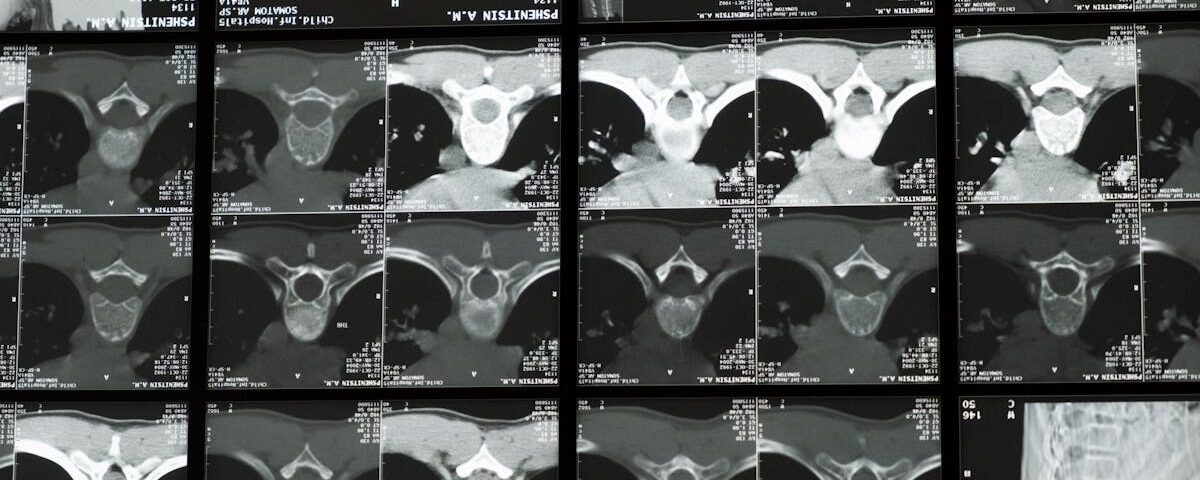

Décompression neurovertébrale : études cliniques sur l’arthrose